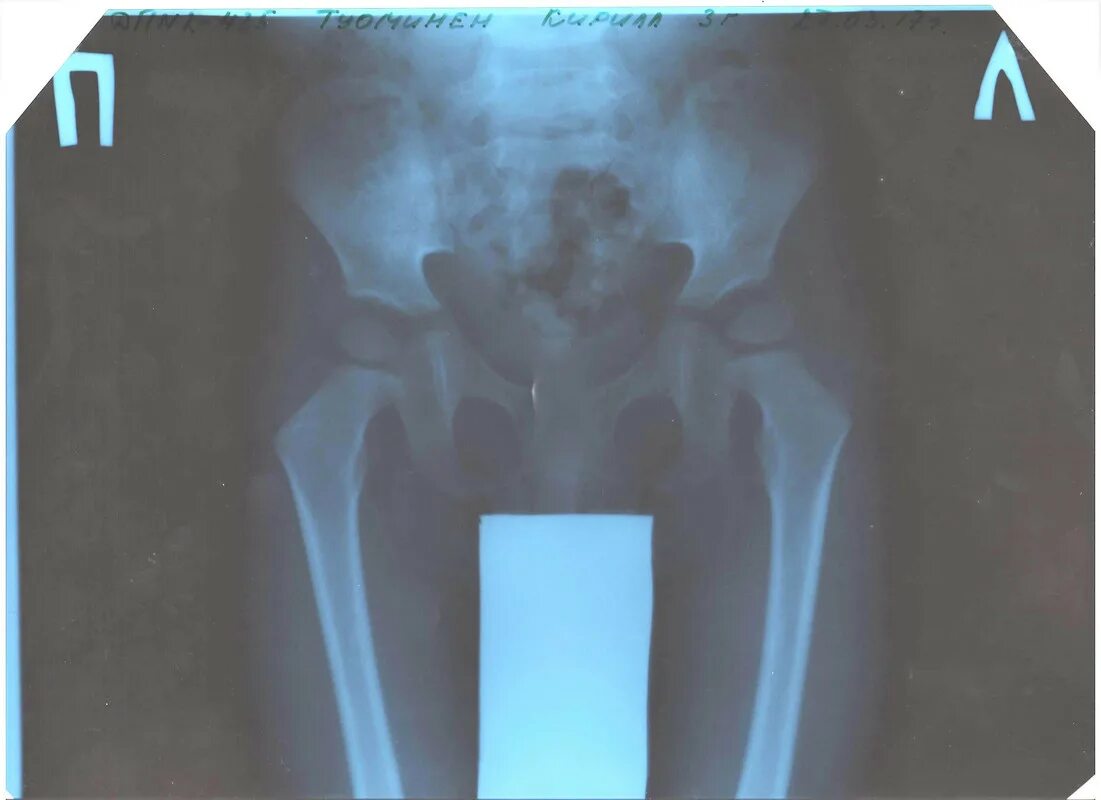

Можно делать рентген при температуре ребенку